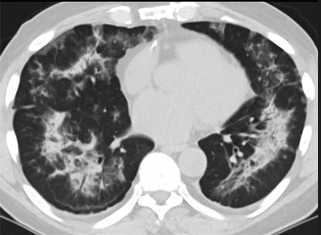

怎么“中度可疑”呢?這些專家表示,這5位患者的肺部CT都具備新冠肺炎CT的影像特征,比如肺部出現(xiàn)磨玻璃的影像,磨玻璃主要分布在雙下肺靠近外周,出現(xiàn)鋪路石征、嚴重的表現(xiàn)為雙肺彌漫性多發(fā)實變。同時,其病程轉(zhuǎn)歸和臨床特征也與新冠肺炎相似。

以下面這4張圖涉及的這個美國“電子煙”病人為例,專家不是僅僅通過一張影片做判斷的,而是通過這4張涵蓋了這名病例肺部多天變化情況的影片進行的研判,認為該病例的病程進展跟新冠更為相似。